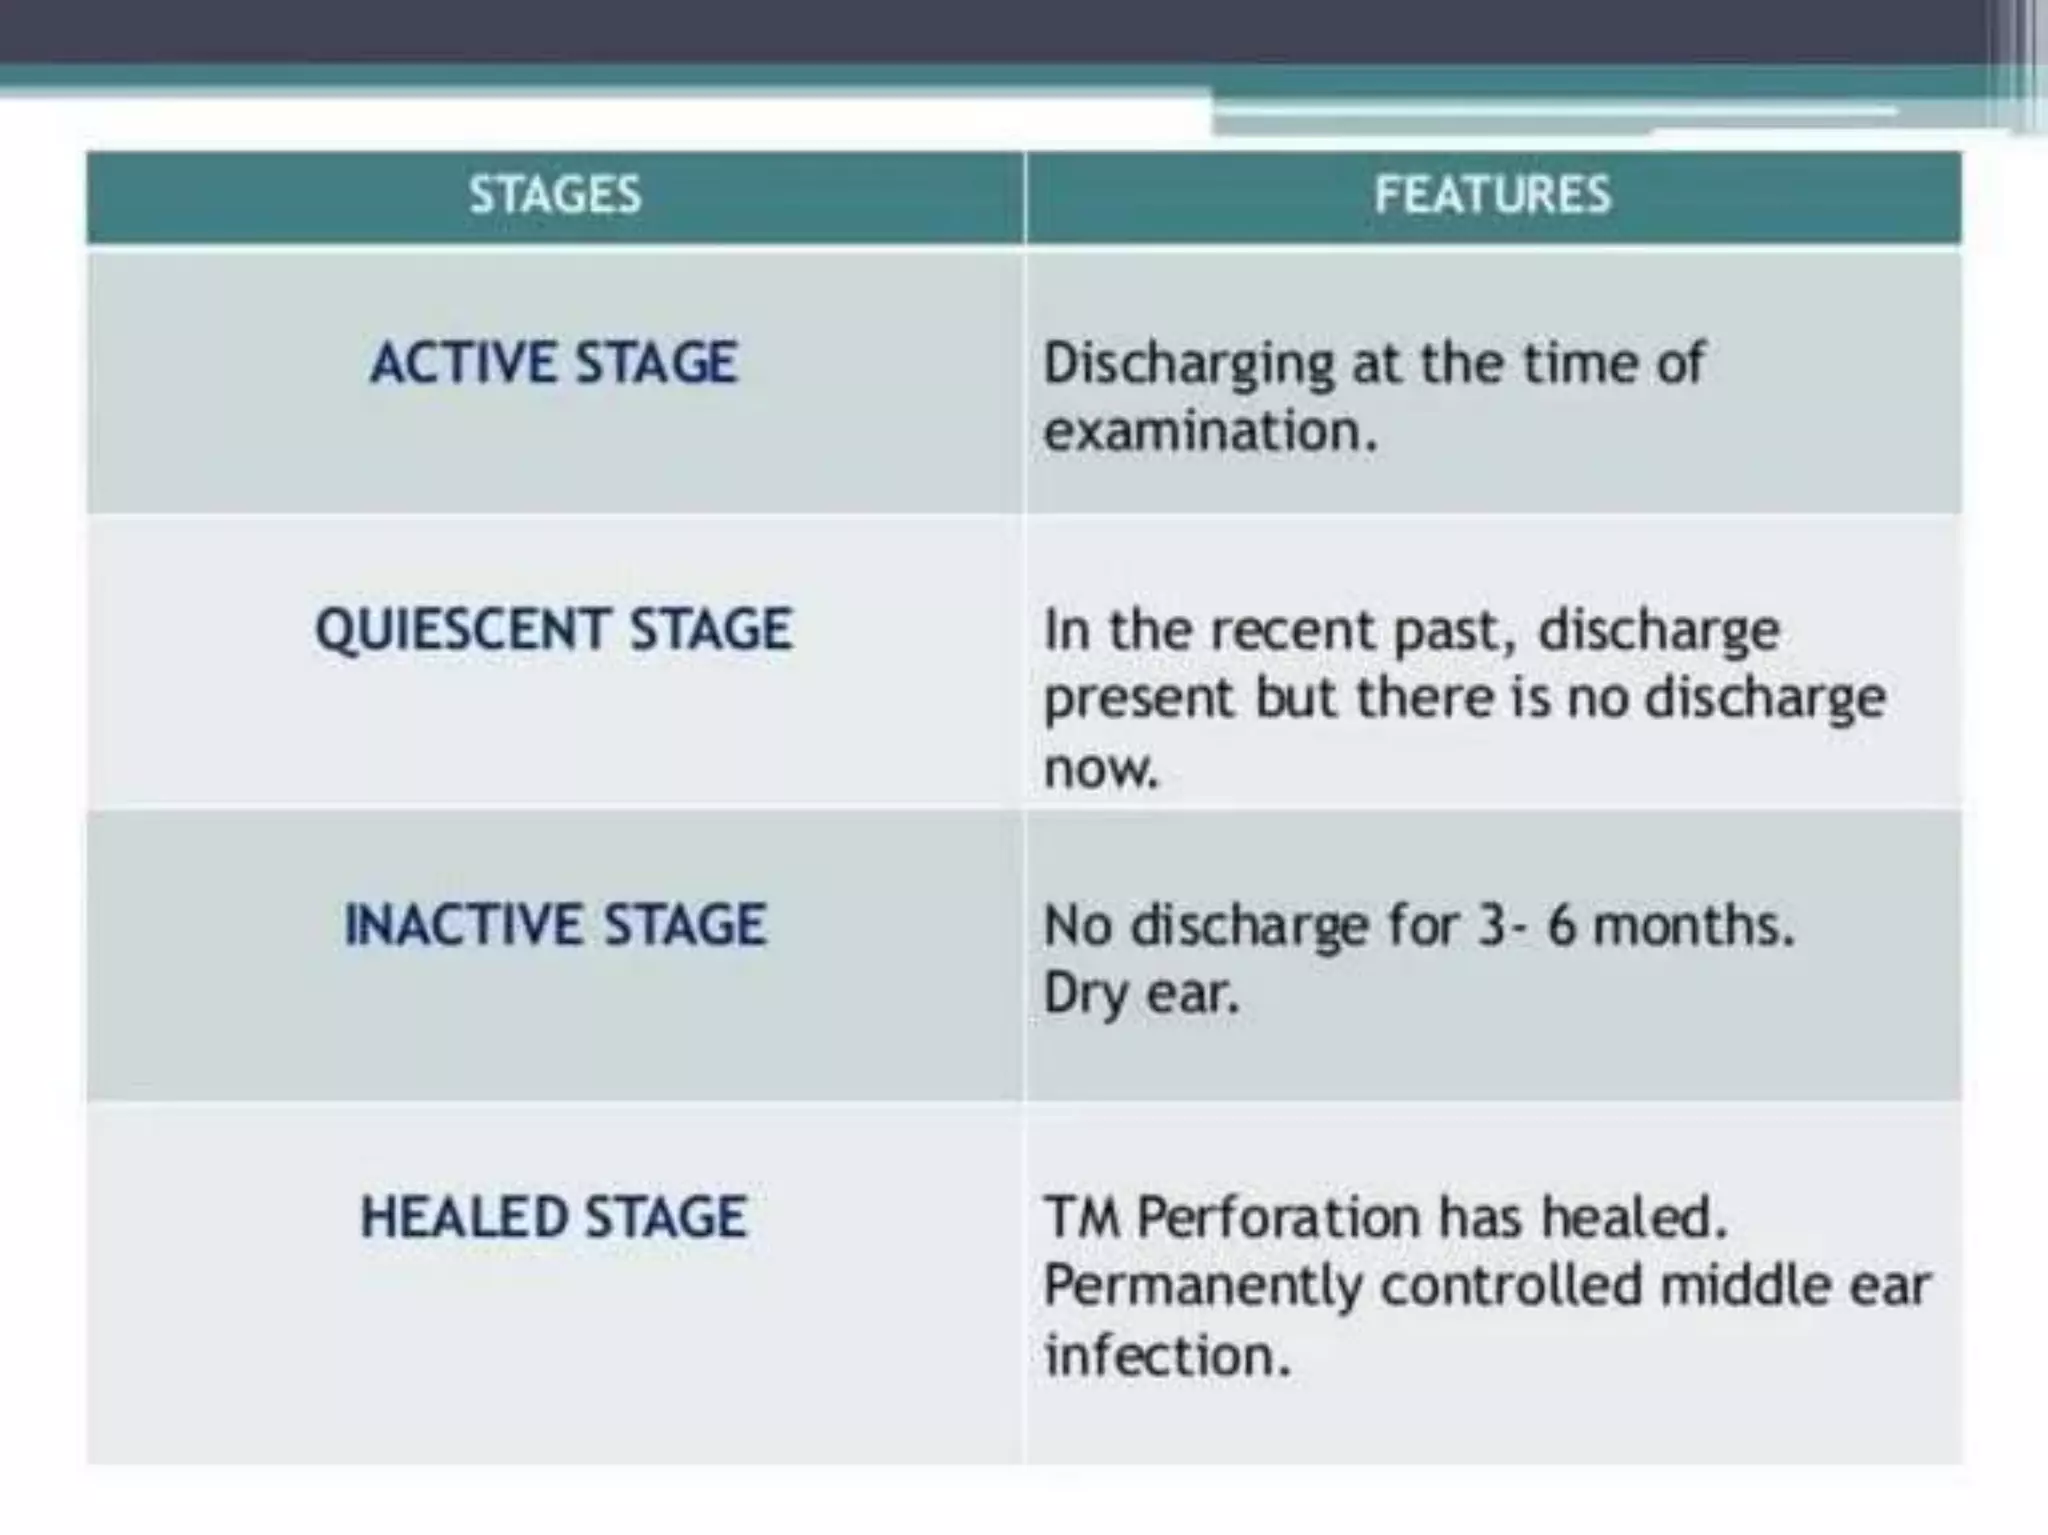

Chronic otitis media is a chronic inflammation of the middle ear and mastoid cavity that presents with recurrent ear discharge through a perforated eardrum. It has several subtypes depending on the state of the eardrum perforation and epithelium. It can be caused by prior acute otitis media, genetics, environment, eustachian tube issues, gastroesophageal reflux disease, craniofacial abnormalities, or immune deficiency.